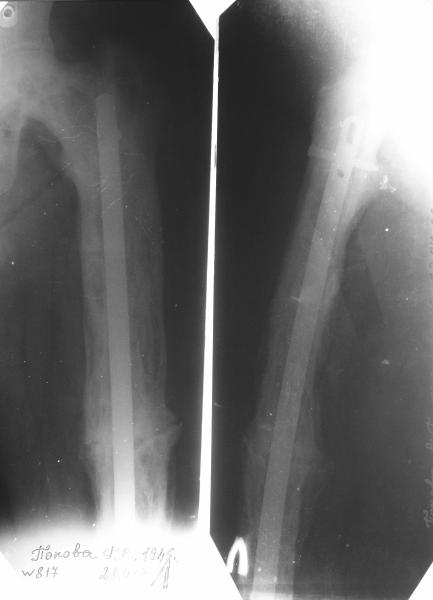

Пациент 82 лет, поступил через 5 мес. с несросшимся переломом после открытого интрамедуллярного остеосинтеза. Выполнили реостеосинтез стержнем 12 мм. ( мах. доступного нам в 2003 г.) Через 4 мес динамизация. В течении 2х лет сращения нет, тем не менее конечность опорна (ходит с тростью). От очередного реостеосинтеза отказались из-за сопутств. патологии.

Еще один пример. Пациентка с юга России, прислала рентгенограммы через год. На сегодня прошло 2 г. 8 мес. после операции. Несмотря на не очень убедительный процесс сращения, пациентка ходит. Учитывая остеопороз при Педжете, решили, что динамизировать вообще не нужно.